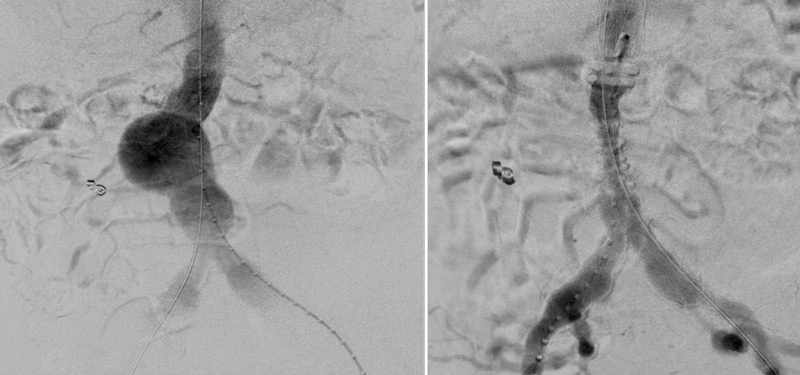

Transcaval embolisation (TCE)

- Transcaval access

- Embolisation of the sac and afferents

- Transcaval embolisation provides an alternative strategy with success rates comparable to other techniques.

- It can be an advantage when the endoleak is on the right side of the sac and/or in recurrent endoleaks.

- Preserving entry to the sac is essential in this type of endoleak.